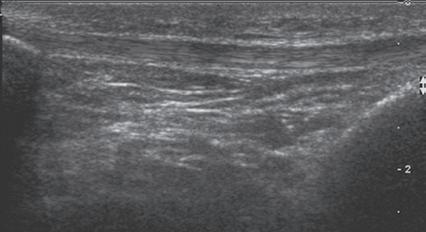

SONOGRAPHIC APPEARANCES OF NORMAL STRUCTURES

Musculoskeletal structures have characteristic appearances on ultrasound imaging.2 Normal tendons appear hyperechoic with a fiber-like or fibrillar echotexture (see Fig. 1.4).3 At close inspection, the linear fibrillar echoes within a tendon represent the endotendineum septa, which contain connective tissue, elastic fibers, nerve endings, blood, and lymph vessels.3 Continuous tendon fibers are best appreciated when they are imaged long axis to the tendon. On such a long axis image, by convention the proximal aspect is on the left side of the image, with the distal aspect on the right. In short axis, normal hyperechoic tendon fibers appear as bristles of a brush seen on end (see Fig. 1.9A). Normal muscle tissue appears relatively hypoechoic (Fig. 1.6). At closer inspection, the hypoechoic muscle tissue is separated by fine hyperechoic fibroadipose septa or perimysium, which surrounds the hypoechoic muscle bundles. The surface of bone or calcification is typically very hyperechoic, with posterior acoustic shadowing and possibly posterior reverberation if the surface of the bone is smooth and flat (Fig. 1.6). The hyaline cartilage covering the articular surface of bone is hypoechoic and uniform (Fig. 1.7A and B), whereas the fibrocartilage, such as the

FIGURE 1.6 Muscle. Ultrasound image of brachialis and biceps brachii muscles in long axis shows hypoechoic muscle and hyperechoic fibroadipose septa (arrows). H, Humerus.